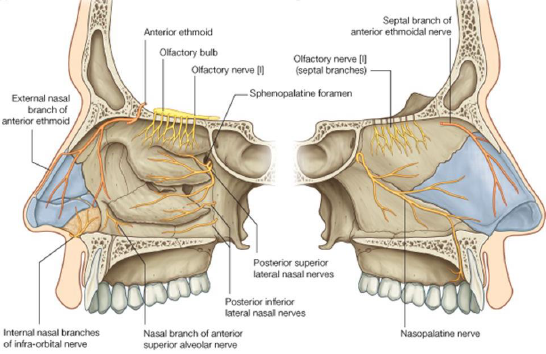

Nerve

- Olfactory n. (CN I)

- Anterior ethmoid n.

- 中下鼻甲前測一般感覺

-

Infraorbital n.

-

- Post. inf. nasal Br. of Greater palatine n.

- Nasopalatine n.

- 走在鼻中隔

- 穿過 Incisive canal

- Post. lat./med. sup. nasal n.